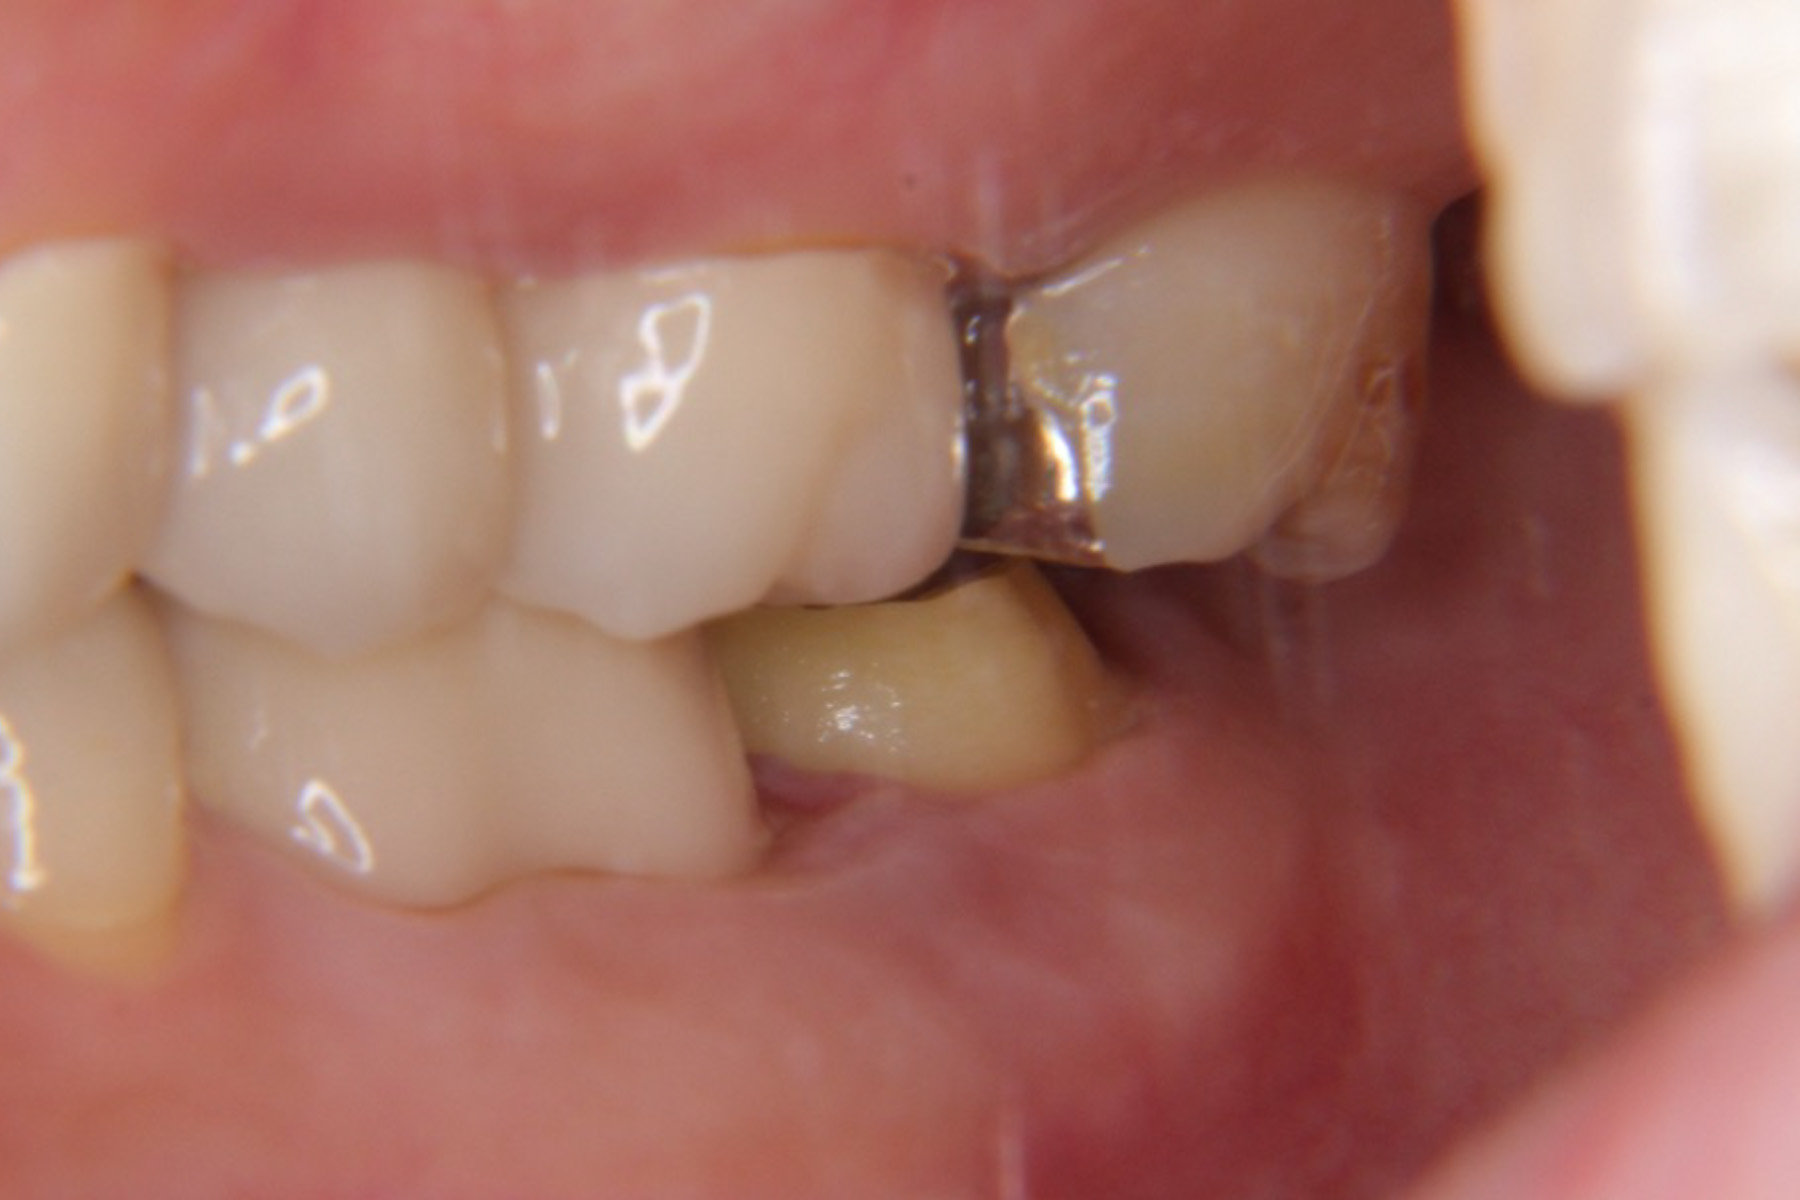

| 主訴 | 右下奥歯が膿んでいる。 |

|---|---|

| 治療内容 | 右下7番は歯根破折により抜歯が推奨された。親知らずの状態も良かった為抜歯と同時に歯牙移植手術を実施し、実質的に機能歯の喪失を防いだ。 |

| 治療期間 | 4〜6ヶ月 |

| 治療費 | 約¥50,000〜 |

| 治療リスク | 生着せず抜け落ちてしまうこともある。 |